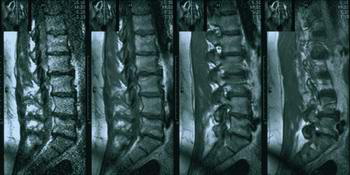

grija2.jpgПример2: В июне 2003 года проведено лечение больной с 5-ью (!) грыжами дисками поясничного отдела. Возраст - 49 лет. Специалисты тех же учреждений настоятельно рекомендовали оперативное лечение. Прошла также лечение по разным методикам, которые консервативным путем обещали избавить от этой болезни. Но настоящее полноценное и высокоэффективное лечение получила после проведения курса лечения по нашей методике, направленной на ликвидацию очагов патологической импульсации.  По состоянию на октябрь 2003 чувствует себя отлично (никаких неврологических проявлений нет).